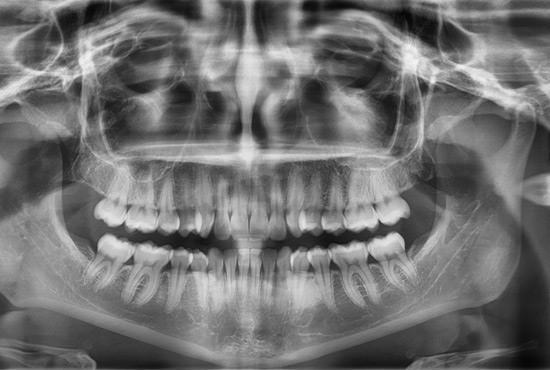

Proporciona una vista panorámica de la estructura dental y maxilofacial, ideal para evaluar el estado general de la mandíbula y los dientes.